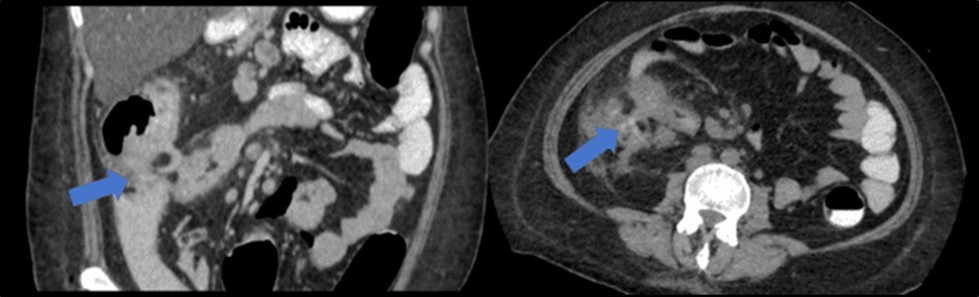

There was no evidence of malignancy or IBD seen during both endoscopic procedures. Computed tomography (CT) scan of the whole abdomen was done which showed inflammatory changes involving the cecum and adjacent duodenum and ileum with coloenteric fistulae. There was noted progression of abdominal lymphadenopathies as well as ascites. Main consideration was an infectious disease process (i.e. TB) (Figure 2, Figure 3, Figure 4 to Figure 5).

Figure 2.Colonoscopy finding of a circumferential, obstructive and nodular mass with areas of necrosis with a pathologic lumen believed to be communicating with the lumen seen on the previous EGD was seen at the proximal transverse which precluded further advancement of the scope

Figure 3.Coronal and axial view of the abdomen, the blue arrows pointing towards the suggestive communication to the ileum.